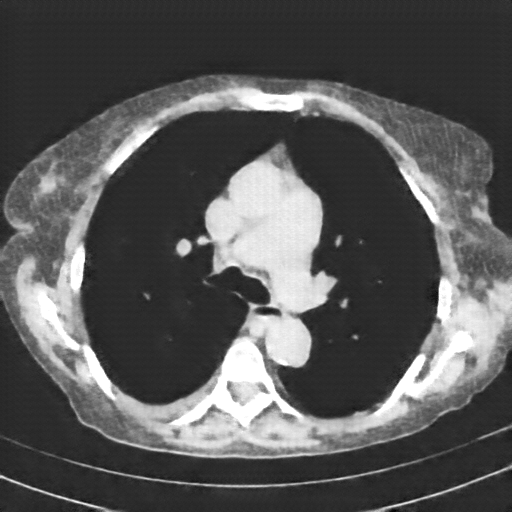

Original VENOUS CT scan

Full window (WL 1023.5, WW 4095 β†’ Low βˆ’1024, High +3071)

Actual HU range: [-160.0, 240.0]